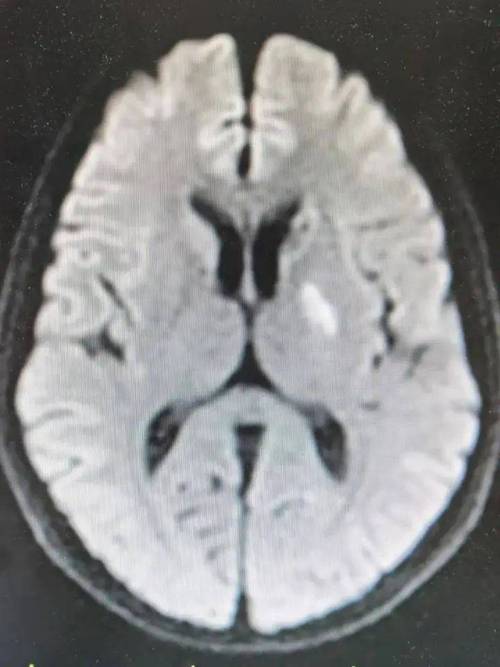

卢脑右侧基底节区腔梗

(图片来源网络,侵删)